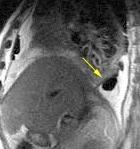

Marzo 2014: Perforación longitudinal distal secundaria a episodio de vómito (síndrome de Boerhaave). Derrame pleural izdo. que evoluciona a empiema.